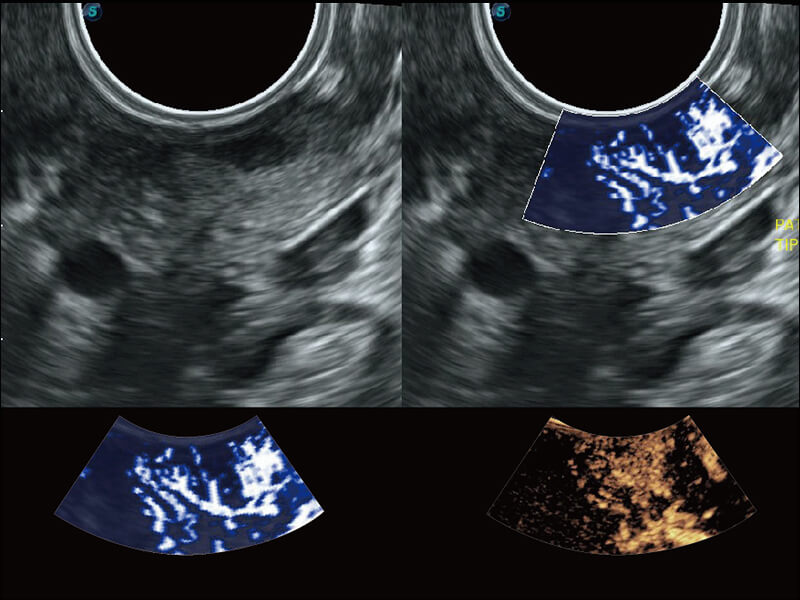

成像功能

超宽频带技术,为容积成像带来优质的二维图像基础,为您呈现丰富的结构细节,栩栩如生地展示宝宝的宫内形态以及各种组织的立体结构。